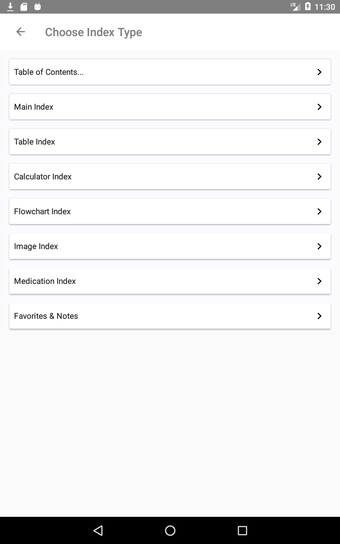

最初に知っておくべきことは、ティンティナリの緊急医療マニュアルが緊急医療の最も重要なトピックについてすべてを提供する包括的なガイドであることです。これは、医師、看護師、および救急医療技師にとって理想的なアプリです。

この無料アプリには、日常の実践に役立つ多くの情報が含まれています。このアプリでカバーされるトピックは、疾患から薬剤、さまざまなタイプの傷害まで幅広く、患者ケアを担当する人々にとって素晴らしいリソースです。